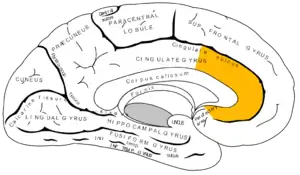

Alcohol acts as a general central nervous system depressant, but it also affects some specific areas of the brain to a greater extent than others. Memory impairment caused by alcohol has been linked to the disruption of hippocampal function—particularly affecting gamma-Aminobutyric acid (GABA) and N-methyl-D-aspartate (NMDA) neurotransmission which negatively impacts long-term potentiation (LTP).[2] The molecular basis of LTP is associated with learning and memory.[3] Particularly, damage to hippocampal CA1 cells adversely affects memory formation,[4] and this disruption has been linked to dose-dependent levels of alcohol consumption.[5] At higher doses, alcohol significantly inhibits neuronal activity in both the CA1 and CA3 pyramidal cell layers of the hippocampus.[6][7][8] This impairs memory encoding,[9] since the hippocampus plays an important role in the formations of new memories.

Alcohol also impairs and alters the functioning in the cerebellum, which affects both motor function and coordination.[27] It has a notable inhibitory effect on the neurons of the cerebral cortex, affecting and altering thought processes, decreasing inhibition, and increasing the pain threshold. It also decreases sexual performance by depressing nerve centers in the hypothalamus.[28][29] Alcohol also has an effect on urine excretion via inhibition of anti-diuretic hormone (ADH) secretion of the pituitary gland. Lastly, it depresses breathing and heart rate by inhibiting neuronal functioning of the medulla.[30]

Alcohol affects the functioning of the brain. Neurochemical changes occurring in the anterior cingulate are correlated with altered short-term memory functions in the brains of young alcoholic men.[40] fMRIs of alcohol-dependent women displayed significantly less blood oxygen in the frontal and parietal regions, especially in the right hemisphere.[41] This is supported by findings of short-term memory impairment by lesions of both the parietal lobe[42] and the prefrontal cortex.[43] Associations between third ventricle volume and cognitive performance on memory tests have been found in alcoholics.[44] Specifically, increases in third ventricular volume correlate with a decline in memory performance.[44]